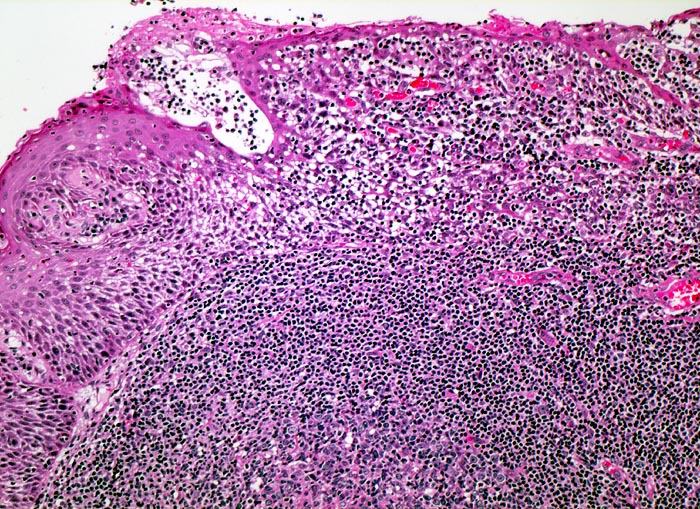

PathoPic – image database / PathoPic ID 4052 - Tonsille mit Sekundärfollikel

Tonsille mit Sekundärfollikel

Ein sekundärer Lymphfollikel mit angeschnittenem Keimzentrum wird bedeckt von Plattenepithel der Mundschleimhaut. Zahlreiche Lymphozyten infiltrieren das darüberliegende Epithel, was in der Tonsille ein Normalbefund darstellt.